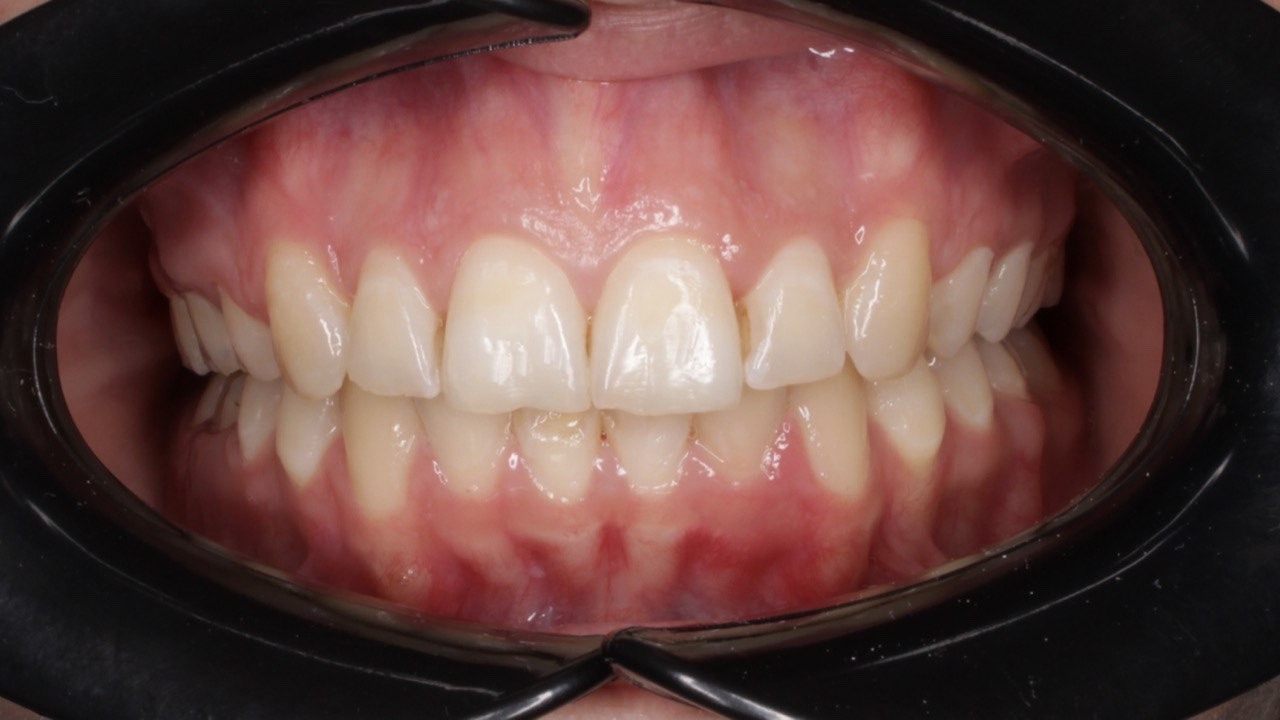

Портфолио - после 2